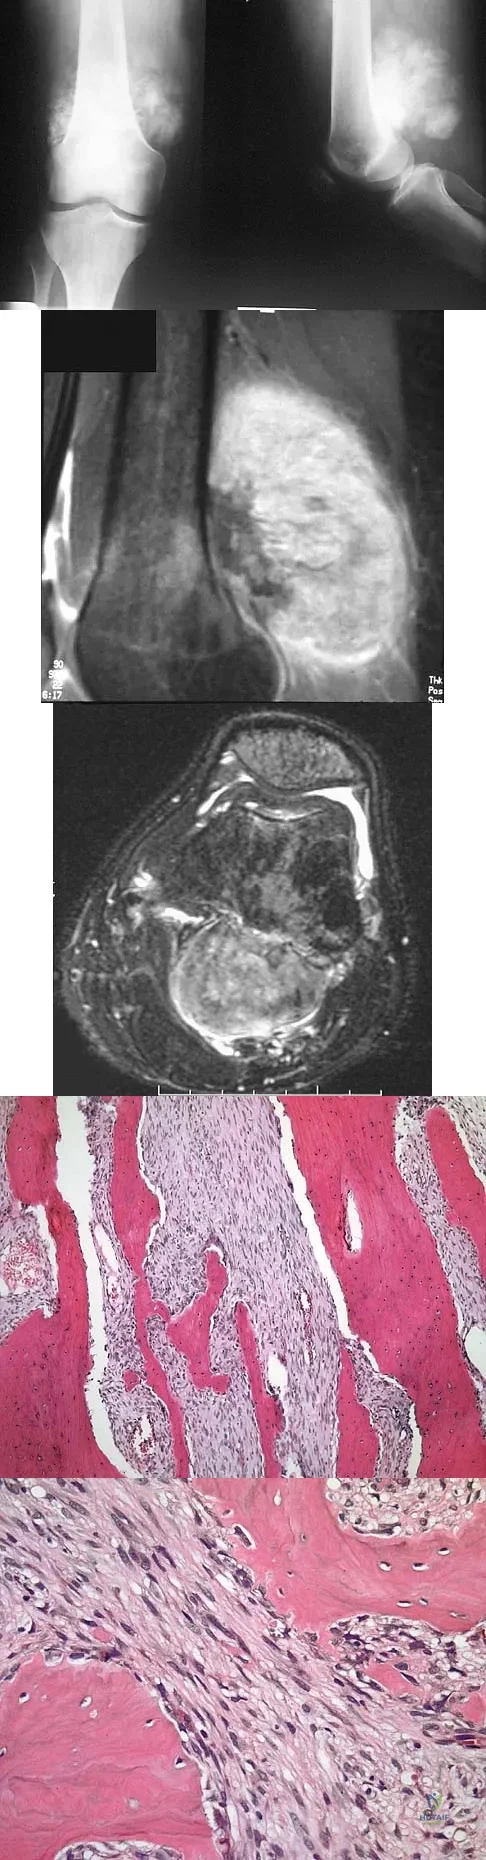

An 18-year-old boy has had pain in the right knee for the past 6 months. Examination reveals some fullness behind the knee but no significant palpable soft-tissue mass. There is no effusion, and he has full knee range of motion. The remainder of the examination is unremarkable. A radiograph and MRI scans are shown in Figures 33a through 33c, and biopsy specimens are shown in Figures 33d and 33e. What is the most likely diagnosis?

Explanation